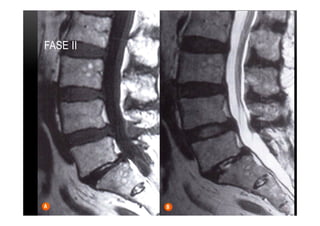

•  Tipo II

•  Alterações caracterizadas por aumento da intensidade do sinal em imagens ponderadas

em T1 e sinal isointenso ou aumentado em imagens ponderadas em T2.

•  Indicam substituição da medula óssea normal por gordura.

•  Tipo mais comum

•  Geralmente estável em 1 a 2 anos, podendendo não evoluir para tipo III

MODIC II

PLATÔS VERTEBRAIS •  TipoII •  Alterações caracterizadas por aumento da intensidade do sinal em imagens ponderadas em T1 e sinal isointenso ou aumentado em imagens ponderadas em T2. •  Indicam substituição da medula óssea normal por gordura. •  Tipo mais comum •  Geralmente estável em 1 a 2 anos, podendendo não evoluir para tipo III